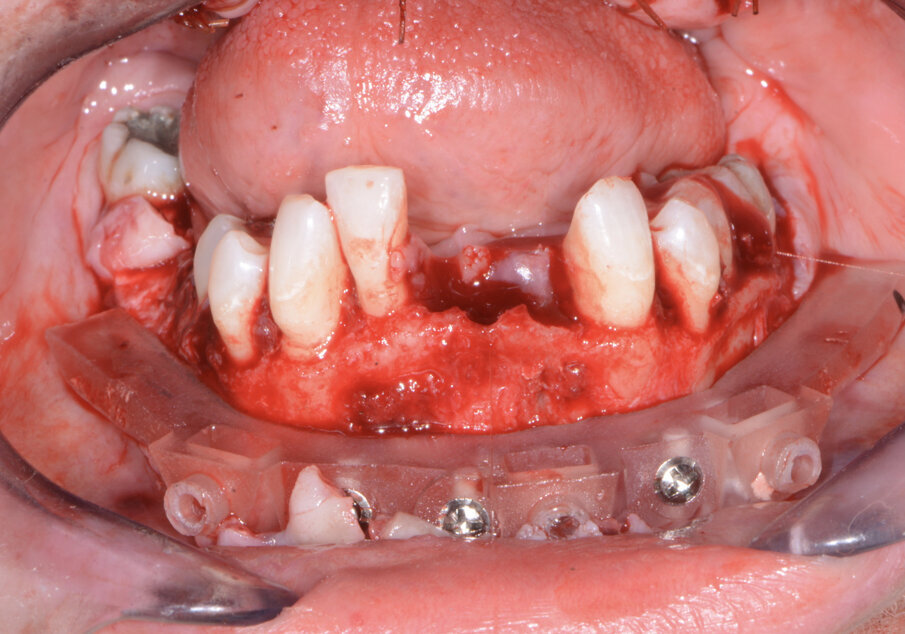

Fig. 12: Mandibular bone levelling foundation guide.

Fig. 13: Mandibular implant surgical guide.

Fig. 14: Mandibular temporary cylinders isolated.

The maxillary provisional restoration was tried in to verify a passive fit over the temporary abutments. Once fit had been confirmed, trimmed dental dam pieces were placed to avoid the restoration (Fig. 11) from locking on during the relining procedure with REBASE III FAST set hard reline material (Tokuyama Dental). After the material had polymerised, the immediate provisional restoration was removed and any access material was removed with the Torque Plus laboratory handpiece (Aseptico) and an acrylic bur (Komet). The same procedures were accomplished in the mandibular arch (Figs. 12–14). Once trimmed and polished, the provisional restorations were seated and tightened with a torque wrench at 15 Ncm (Fig. 15). The access openings were filled in three-quarters of the way with Teflon tape, followed by Cavit filling material (3M ESPE). A postoperative panoramic radiograph was taken immediately after the surgery (Fig. 16).